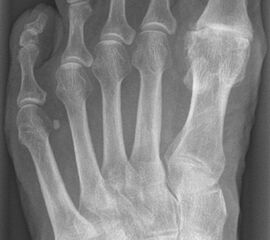

• Röntgenaufnahmen des Vorfußes (unter Belastung) im dorsoplantaren und seitlichen Strahlengang (Abb. 1a+b)

• Beurteilung des Erkankungsstadiums anhand der typischen Arthrosekriterien (Einteilung nach Regnauld). Beurteilung des Intermetatarsal-Winkels (IMA), des Hallux valgus-Winkels (HVA), da nur geringe Korrekturmöglichkeit durch die Osteotomieebene, darüber hinaus evtl. zusätzliche basisnahe MT-I-Korrektur notwendig

• Beurteilung der Grundgliedlänge, insbesondere nach Voroperationen, hinsichtlich möglicher Überlänge des Implantat-Stems.